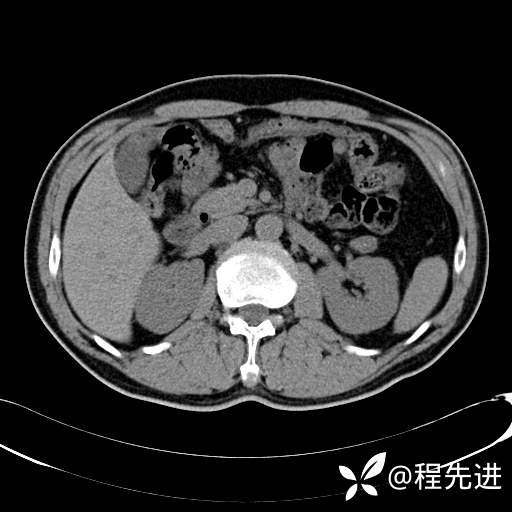

患者性别:男

患者年龄:65岁

简要病史:腰痛2月,体检发现左肾占位5天

平扫: